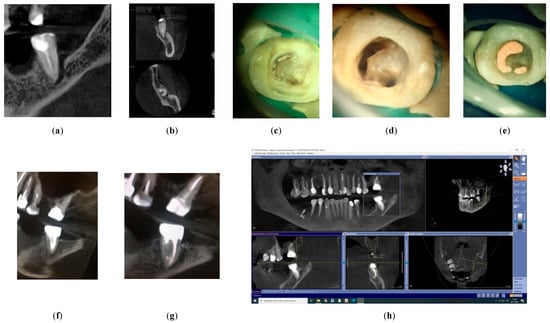

2.1. Clinical Case 1

2.2. Clinical Case 2

2.3. Clinical Case 3